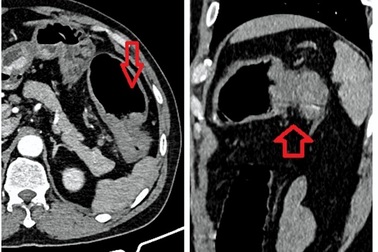

Phát hiện u trực tràng khủng nhờ dấu hiệu đi đại tiện khóBệnh nhân thường xuyên có biểu hiện đi đạ tiện khó, khuôn phân dẹt, có nhầy máu… nhưng phải đến khi người mệt mỏi, sút cân mới đến viện. Các bác sĩ phát hiện khối u trực tràng với kích thước lên đến 5,5cmx 13,5cm.